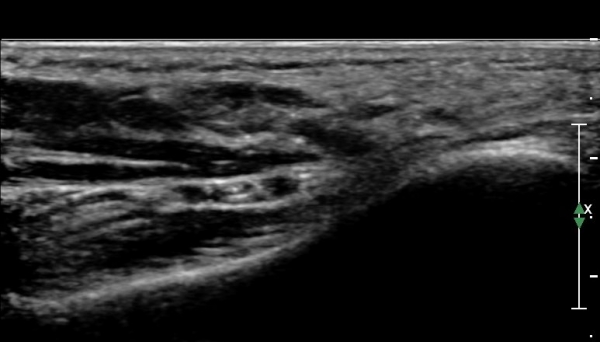

ŽÃËÀÚ¸¦ Á¶±Ý ´õ ¹ß¹Ù´ÚÃøÀ¸·Î À̵¿ÇÏ´Ï ¾Æ·¡µÚ²ÞÄ¡½Å°æÀÌ Àú¿¡ÄÚ µ¢¾î¸® ¸ð¾çÀ¸·Î °üÂûµÈ´Ù

(»çÁø 3, 4)